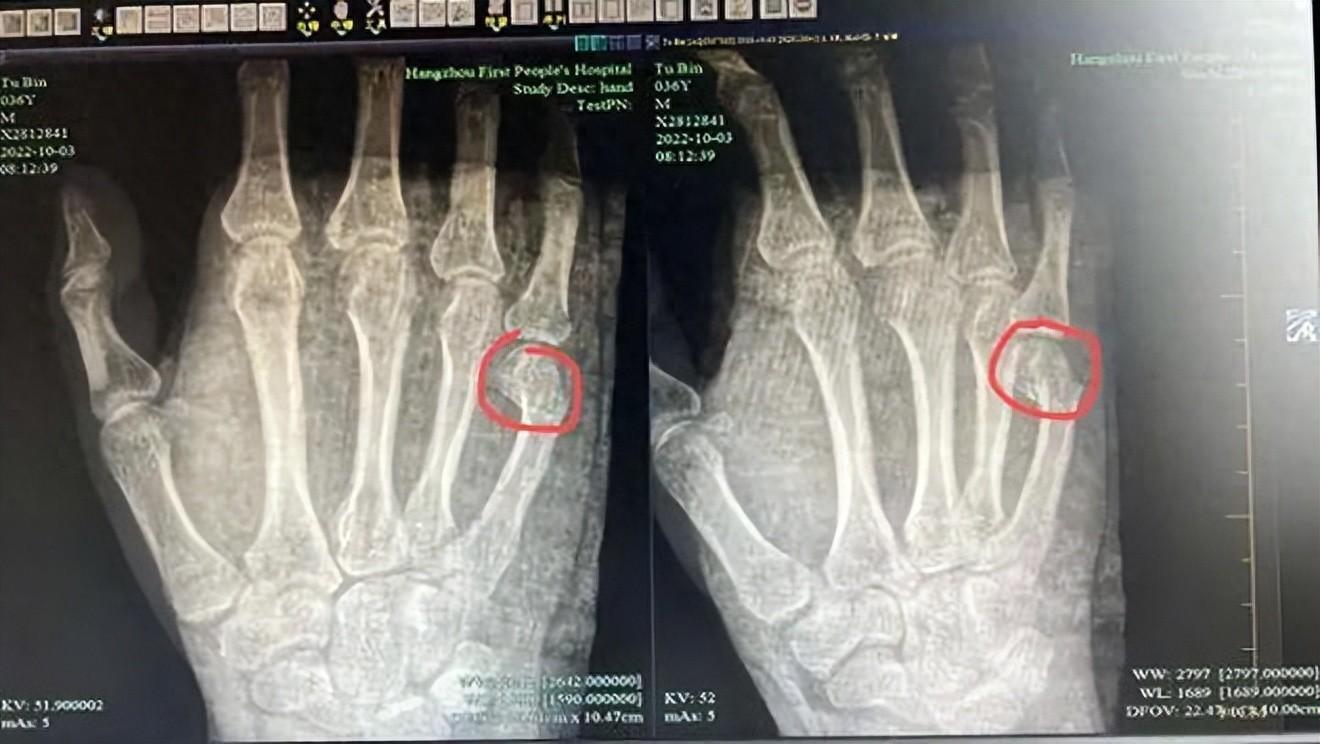

因爲寫作業,氣到乳腺結節,甲狀腺結節;

因爲寫作業,氣到拍桌子手掌骨折;